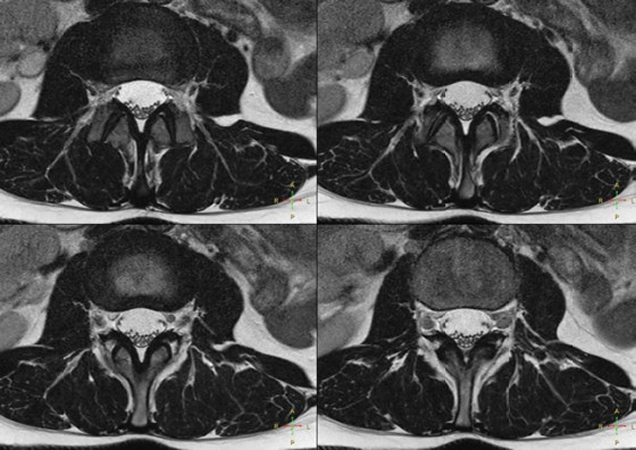

Comprehensive Lumbar Spine imaging at 1.5T

Meander Medical Center, Amersfoort, The Netherlands